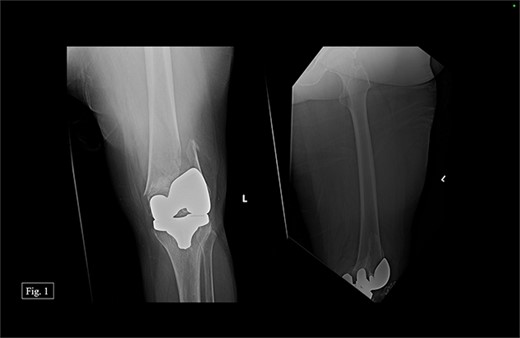

The previous medial parapatellar approach was used to identify and shell out the fractured DF with an arthroplasty component end block. Press fit trials were used, and the contralateral knee joint height was compared. We used the DePuy Synthes MBT revision metaphyseal sleeve, tibial tray rotating platform, MBT revision cemented, limb preservation system (LPS) tibial insert hinge, LPS distal femoral component, LPS sleeve adapter to distal femoral component, universal femoral sleeve, and a universal fluted stem. The patient experienced 1000 mL of intraoperative blood loss, awoke without incident, and was admitted to the ICU for monitoring and management. Postoperative anterior–posterior (AP) and lateral X-rays were taken (Fig. 2).